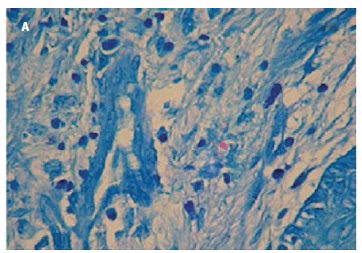

O material para exame histopatológico foi obtido através da retirada de pequeno fragmento (3x3x2 mm) da borda temporal da lesão necrótica do canto medial, e evidenciou reação inflamatória granulomatosa com acúmulo de histiócitos. Ao Fite-Faraco: presença de bacilos álcool-ácido resistentes (2+/3+) Figura 2 A) em globias compatível com hanseníase virchowiana (Figura 2 B).